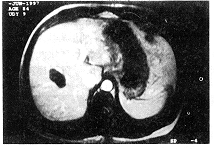

3.CT:平扫CT显示病灶为相对于肝实质的低密度结节,边界清楚(图3);增强后动脉、门静脉期均无强化,延迟像显示5个病灶边缘部轻度强化。4例提示为良性病灶,其余均疑原发或转移性肝癌。

图1 病理示SNN边缘部层次分明,上层为正常肝组织,中层为炎性细胞浸润的纤维包膜,下层为无组织细胞结构的凝固坏死(HE ×200)图2 SNN的B超像,剑突下垂直切面示左外叶边界清楚的低回声结节,内部回声欠均匀 图3 平扫CT示右肝前叶下段内部均匀低密度的SNN结节,CT值32HU 图4 右后叶上段SNN,SE T1WI示葫芦状略低信号结节 图5 同图4病例,SE T2WI示病灶信号相对低于肝实质 图6 同图4病例,Gd-DTPA增强后SE T1WI延迟扫描,病灶无强化,边缘清楚 图7 右叶SNN,平扫SE T1WI示长椭圆形边界清楚的低信号结节,中央有更低信号的“核” 图8 同图7病例,T2WI示中央的“核”呈明显高信号,与门脉分支相似,外周部分与肝组织等信号图9 同图7病例,快速小角度激发(FLASH)序列Gd-DTPA增强后30秒内扫描,病灶无强化,隐约可见如“红枣”的切面